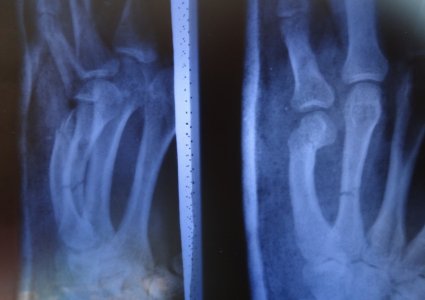

После этого я отходил 5 недель со дня репозиции, сняли лонгету, и сделали снимок:

Доктор сказал что сращения нету вообще, опять наложилли лонгету и сказал ходить ка минимум еще две недели только согнули пальцы немного под углом и уже на 3,4 и 5 палец плюс назначил магнитотерапию (вроде так, точно не помню) , вот фото лонгеты: